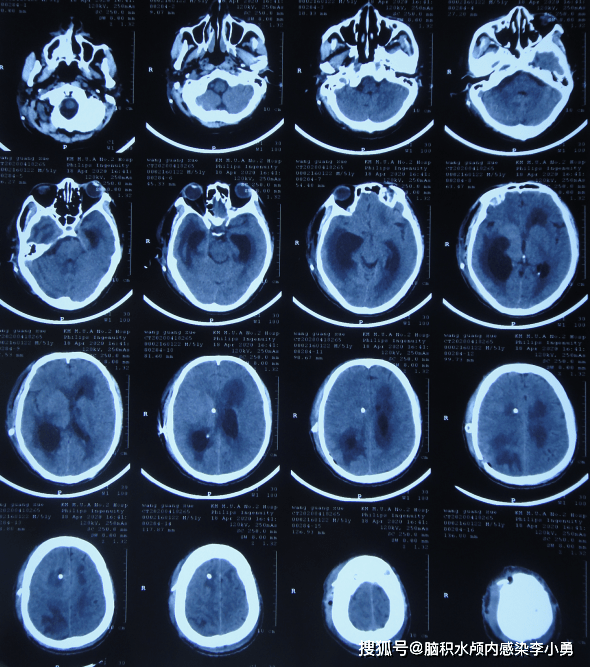

2021年5月23日头颅ct在该院治疗88天即2021年5月25日(脑外伤后脑出血

急送往当地的河北省邯郸市的某三甲医院,查头颅ct示脑挫裂伤

进行了脑室外引流术,术后次日即2020年7月31日,查头颅ct示脑积水术后

图-4:2019年2月21日头颅ct但脑出血脑室外引流术3天即2019年2月21日